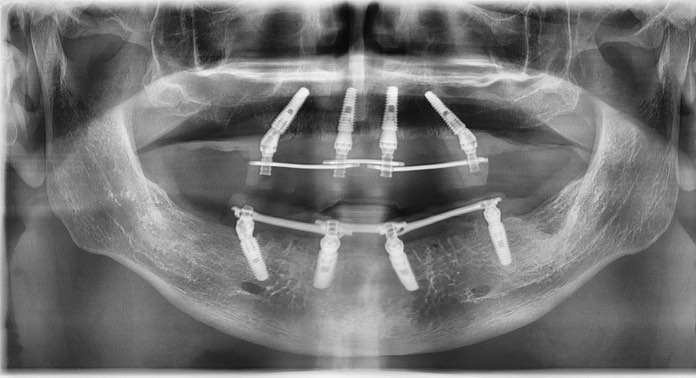

Тотальная имплантация AnyOne методом all-on- 4.

Иващенко Александр Николаевич: клинический стоматолог-хирург, практикующий имплантолог.